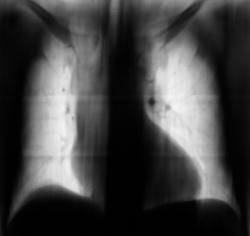

Пациент "взят на контроль". Подозрительным показалось расширение тени средостения вправо. Произведено стандартное дообследование пациента - рентгенография в прямой и правой боковой проекциях, произведена томография в прямой проекции.

Ваше мнение уважаемые коллеги.

Я бы подумала, что это тень восходящей аорты.

Или верхней полой вены?